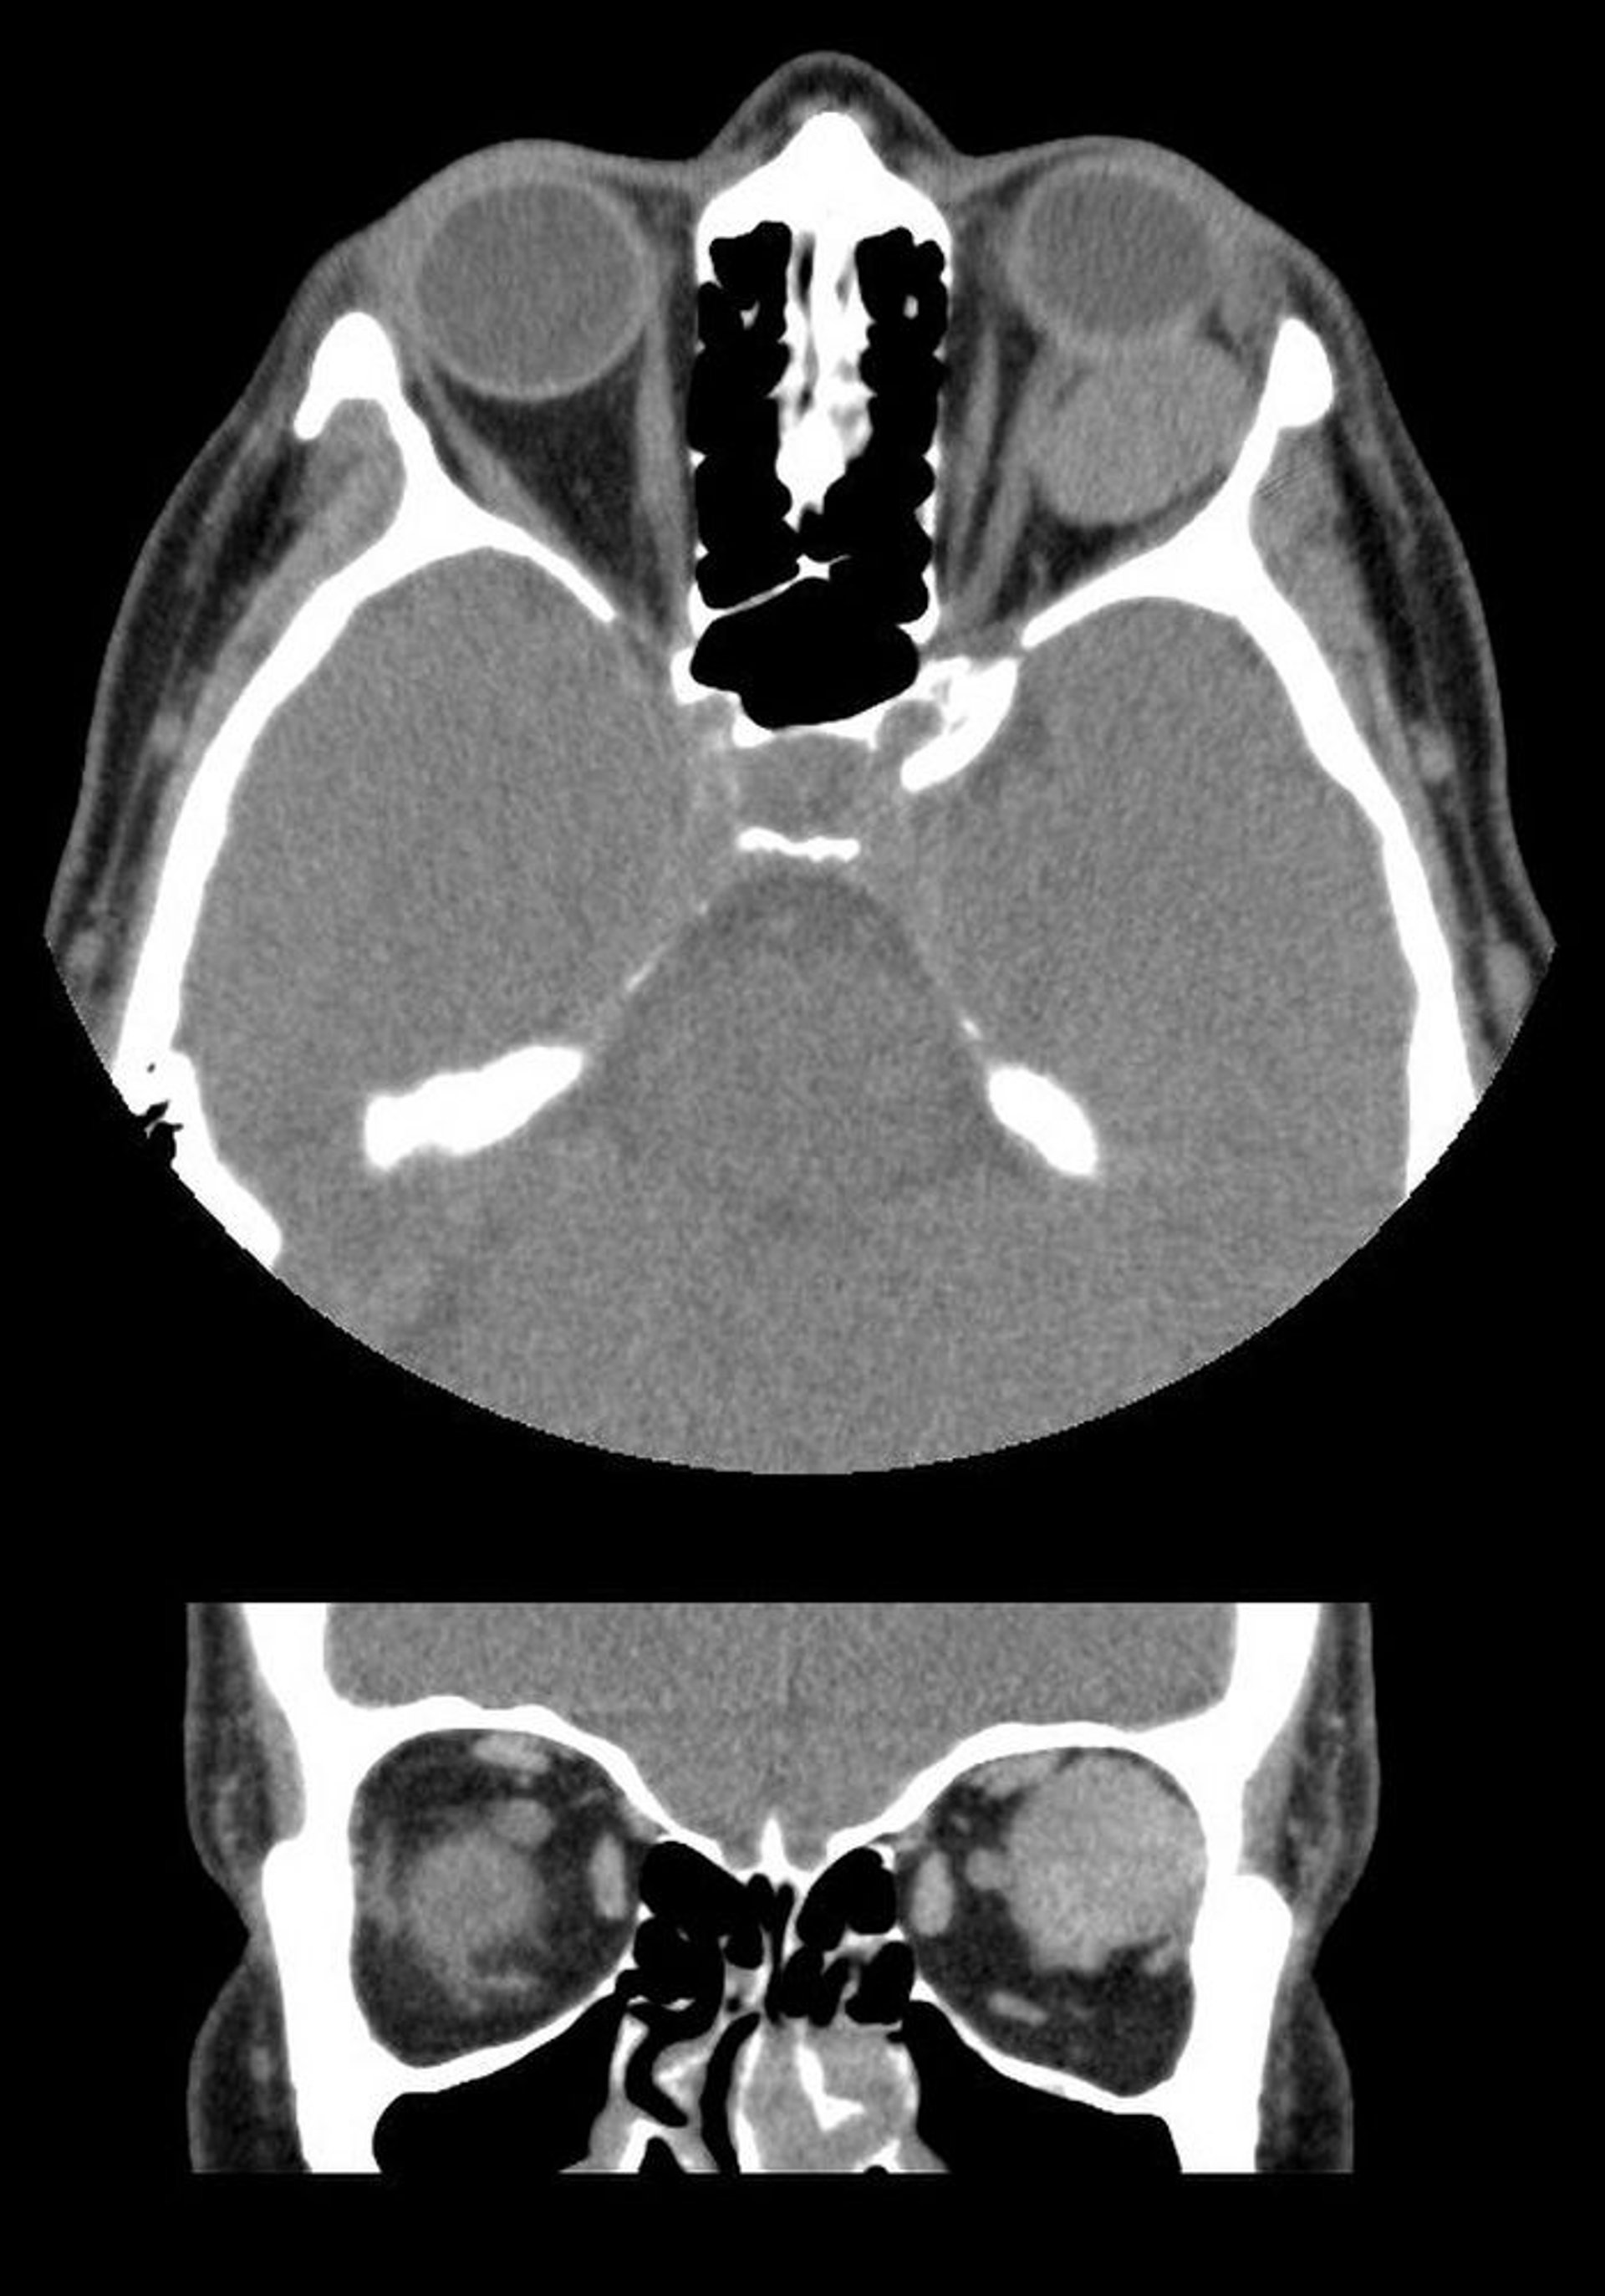

Hémangiome caverneux

Dans cette image, les TDM axiales (en haut) et coronales (en bas) montrent une masse intraconale bien délimitée située derrière le globe gauche. La masse est une malformation veineuse caverneuse.

Images courtesy of James Garrity, MD.